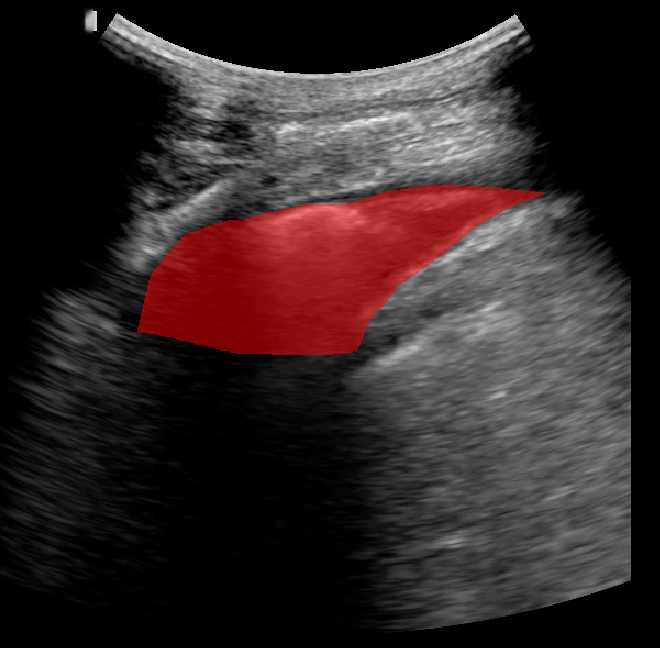

A total of 143 images were acquired from 59 patients. The images were obtained at the left and right PLAPS (PosteroLateral Alveolar and/or Pleural Syndrome) and subcostal views [4] with linear array and curved array (abdominal) ultrasound probes. The data were split according to the use of these probes into two datasets of 51 and 92 images, respectively for linear array and curved array. We denote these datasets as Dataset A (linear array) and Dataset B (curved array). All images were annotated at the time of acquisition to measure the extent of the effusion. These annotations consisted of small crosses at the top and bottom of the deepest area of effusion. See Figure 1 (left column) for example images.

Before being used for training and evaluating the models, each image was automatically cropped using a rectangular/cone mask to remove non-imaging content. Next, we applied an inpainting text algorithm using keras-ocr followed by template matching and edge detection algorithms from opencv to remove the annotations that were added to the images to measure the effusion. Examples of the outputs of this preprocessing are shown in Figure 1 (centre column).

All images in both datasets were manually segmented using the ITK-SNAP software [14] (www.itksnap.org) by a trained observer. Examples of ground truth segmentations are shown in Figure 1 (right column). These segmentations acted as ground truths for training and evaluating the proposed models. Additionally, a second trained observer performed independent segmentations of subsets of 10 random images each from the two datasets. These were used to compute an estimate of inter-observer variability in the manual segmentation process.

Qualitative prediction results of the two proposed models (baseline nnU-Net and nnU-Net with coordinate convolutions) on the two datasets are shown in Figure 2. Tables 1 and 2 summarise the quantitative performances in terms of DSC and area statistics. Histograms of the DSC values are shown in Figure 3. The median DSCs between the manual segmentations on the subsets of 10 images (i.e. the estimates of inter-observer variability) are also shown in Table 1.

Rows 1-2: Dataset A. Rows 3-4: Dataset B.